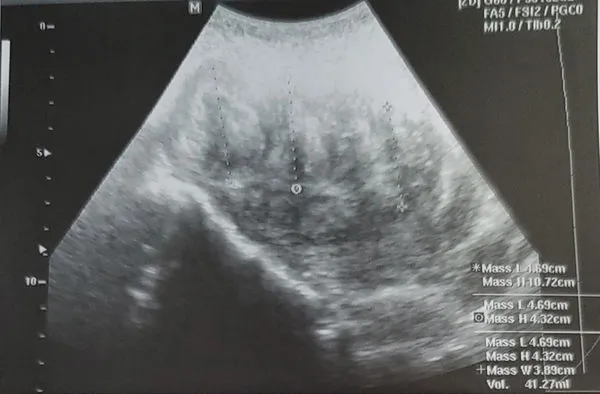

▲▼宜蘭葉姓婦女超音檢查最大肌瘤在子宮宫底(上圖),另外3個肌瘤分別在子宮後壁和子宮頸後(圖/陽明交大附醫提供,下同)

陽明交大附醫表示,宜蘭37歲葉姓婦女因經痛、經血多和頻尿到婦產科門診就醫,超音波檢查發現4個子宫肌瘤,大小分别是10.6,4.6 ,4.3和3.6公分,最大的在子宮宫底,平時下腹就可摸到,另3個肌瘤的位置比較不尋常在子宮後壁和子宮頸後骨盆腔深處。